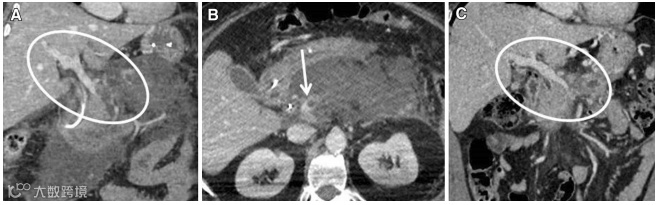

(图源自文献)

A,一例65岁胰腺炎患者,冠状位CT提示:门静脉和肠系膜上静脉部分和完全血栓形成(圆圈)。

B,轴位CT提示:在门-脾-肠系膜静脉汇合处(箭头)可见局灶性血栓形成,这与胰腺坏死积聚有关。

C,抗凝治疗后6个月的冠状位CT提示:门静脉和肠系膜上静脉完全再通,胰周坏死积聚的面积缩小(圆圈)。